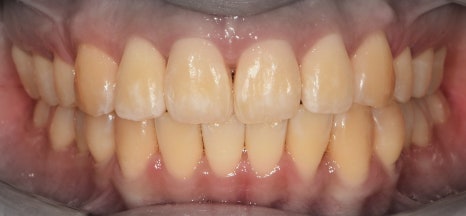

이 분은, 돌출입의 정도가 심했기 때문에

정면에서 본 모습에서도 입술의 긴장감이

같이 느껴지는 분입니다.

그리고, 구치부의 교합력이 다른 사람보다

더 높으신 분이였습니다.

그러면서, 대략 2년이라는 시간이 흘러서

가지런한 치열이 탄생이 되었습니다.

앞서, 1치대 1치 관계에 있던 교합관계들이

1치대 2치의 관계로 바뀐것을 볼 수 있으면서

길쭉하게 느껴졌던, U shape 형태의 악궁이

딱 보기 좋은, U shape 로 바뀌었죠.